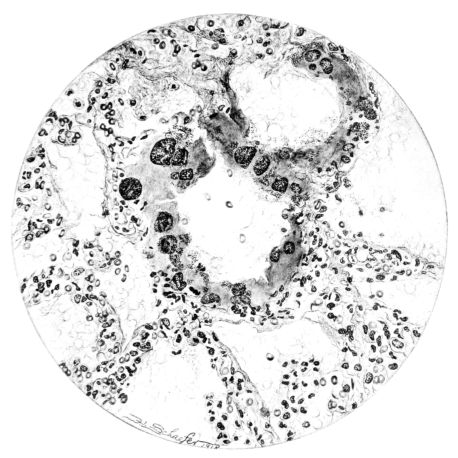

FIG. III. AUTOPSY NO. 90. DRAWING FROM A LESION OF THE TRACHEA (SOMEWHAT OLDER THAN THAT ILLUSTRATED IN FIGURE II). THE MUCOSA IS ENTIRELY LACKING. CONGESTION AND EDEMA ARE THE STRIKING FEATURES IN THE SUBMUCOSA. THE NECROTIZING PROCESS HAS EXTENDED INTO THE MUCUS GLANDS. THIS IS SHOWN IN THE LOWER PICTURE.

The changes are less marked, perhaps, in the trachea than in its finer ramifications. The mucosa is constantly more or less destroyed and large areas, usually focal, are entirely devoid of their epithelial covering. This is replaced by a sparse exudate, composed largely of red blood cells, mucus, a small amount of fibrin, and nuclear fragments (Fig. II). It may dip into the submucosa for a short distance, but usually these indentures are associated with the ducts of the mucous glands into which the inflammatory reaction extends. A more striking feature than the exudate, however, is the edema and the congestion of the submucosa. The loose areolar tissue of the submucosa is spread widely apart, and throughout it distended blood vessels are very conspicuous. Occasionally such a vessel is broken and actual hemorrhage appears in the submucosa. Occasionally, too, the inflammation extends down the duct to the mucous gland itself, and here, also, aplastic inflammatory reaction is evident, inasmuch as the acini now stain intensely red with the cells undifferentiated from each other and specked here and there by broken remains of the dead nuclei (Fig. III). After the disease has continued for a short period, even at the end of five or six days, some regeneration of the epithelial lining may be seen (3) (Fig. IV). But despite this, the acute picture persists, and there goes on, side by side, an attempted repair characterized by epithelial regeneration and the same evidence of acute change. Since the lesion is essentially a superficial one, scars or contractures of any extent are not encountered in the trachea, even in examples of the disease that have ended fatally only after many weeks.[4]

15There is considerable evidence to support the view that the disease spreads from bronchus to bronchus, and in keeping with this view, various stages in the inflammatory processes are more readily determined in these smaller structures than in the trachea. Furthermore, it must be emphasized that even the mildest and the most extreme of these stages are not infrequently encountered in the same lung. The earliest lesion is manifested by an increased homogeneity of the protoplasm of the epithelial lining of the bronchus. The cell protoplasm loses its normal granulation and the nucleus, somewhat darker than usual, becomes conspicuous on a red base (Fig. V). In the lumen of such a tube a serous exudate, perhaps mixed with mucus, is encountered, and there is some spreading apart of the surrounding muscular tissue with engorgement of the vessels. This picture merges gradually into one where the epithelium appears as a homogeneous, red-staining ribbon, devoid of nuclei, often exfoliated, in part at least, from the underlying submucosa (92). The change is traceable through the larger bronchi, even to the ducti alveolares, and not infrequently, bacteria, either as a diffuse, minute dotting or in the form of circumscribed, colony-like formations, are spread through the red, ribbon-like strand (Fig. XVI). With the exfoliation of the epithelial lining, the submucous vessels become more and more conspicuous and may bulge into the lumen of the tube (Fig. VI). That they actually weep into the lumen is proved by the presence of red blood cells in the exudate, now rich in mucus, broken-down nuclei, and desquamated cells. The necrotizing process may not extend deeper than the epithelial lining as is the status described above (140, 162), but it also frequently involves the underlying submucous and muscular layers, so that these lose their identity and stand out as homogeneous masses, in which fragmented nuclei and bacterial accumulations are prominent. Such deeper necrotizing areas may be focal (Fig. VII), or may involve the entire circumference of the tube (Fig. VIII). Occasionally, the epithelium, now dead and staining homogeneously, is lifted from the underlying submucosa in the form of a blister (66), and has very much the same appearance as the well known, early reaction which follows the application of croton oil to the rabbit’s ear. Where this occurs, the submucosa is less involved, as though the necrotizing agent had not penetrated to the same depth and the serous reaction beneath were actually a beneficent exudate. These blisters are in contrast with the deeper areas where the fibrinous mass, mixed with the dead tissue, forms an intensely staining ring or band, which extends through the bronchiolar wall even to the surrounding alveoli.